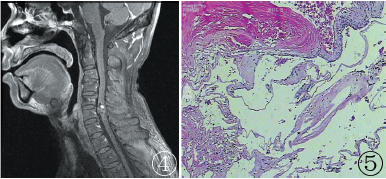

MRI表现:C5~C6段脊髓内见一大小约0.6 cm×0.6 cm×1.5 cm混杂信号影,T1WI呈混杂等/稍长信号,其内可见小结节状高信号影(图1),T2WI呈混杂稍长信号影,病灶边缘可见低信号环(图2),病变节段脊髓稍增粗,周围蛛网膜下腔变窄;病变增强呈中度不均匀强化表现(图3,4)。术中所见:显微镜下沿脊髓后正中切开脊髓组织后,见脊髓组织肿胀,水肿较重,占位周围见暗红色陈旧性出血,占位呈红褐色,与周围组织分界欠清,完整切除占位约1.0 cm×1.0 cm×1.0 cm,质地较硬。病理:灰白灰褐色不整形组织1块,体积1.0 cm×0.5 cm×0.5 cm,(C5~6髓内占位)病变符合脉管瘤伴混合血栓形成(图5)。

图1 矢状位T1WI示病灶呈稍长信号影,其内可见结节样高信号,提示出血可能;图2矢状位T2WI示病灶呈稍长信号为主的混杂信号影,T1WI像上结节高信号影在T2WI像上亦呈稍高信号表现;病灶周围可见环形低信号影,提示含铁血黄素沉积可能;图3,4T1WI增强示病灶信号不均,呈中度不均匀强化表现;图5病理诊断符合脉管瘤伴混合血栓形成(HE×200)